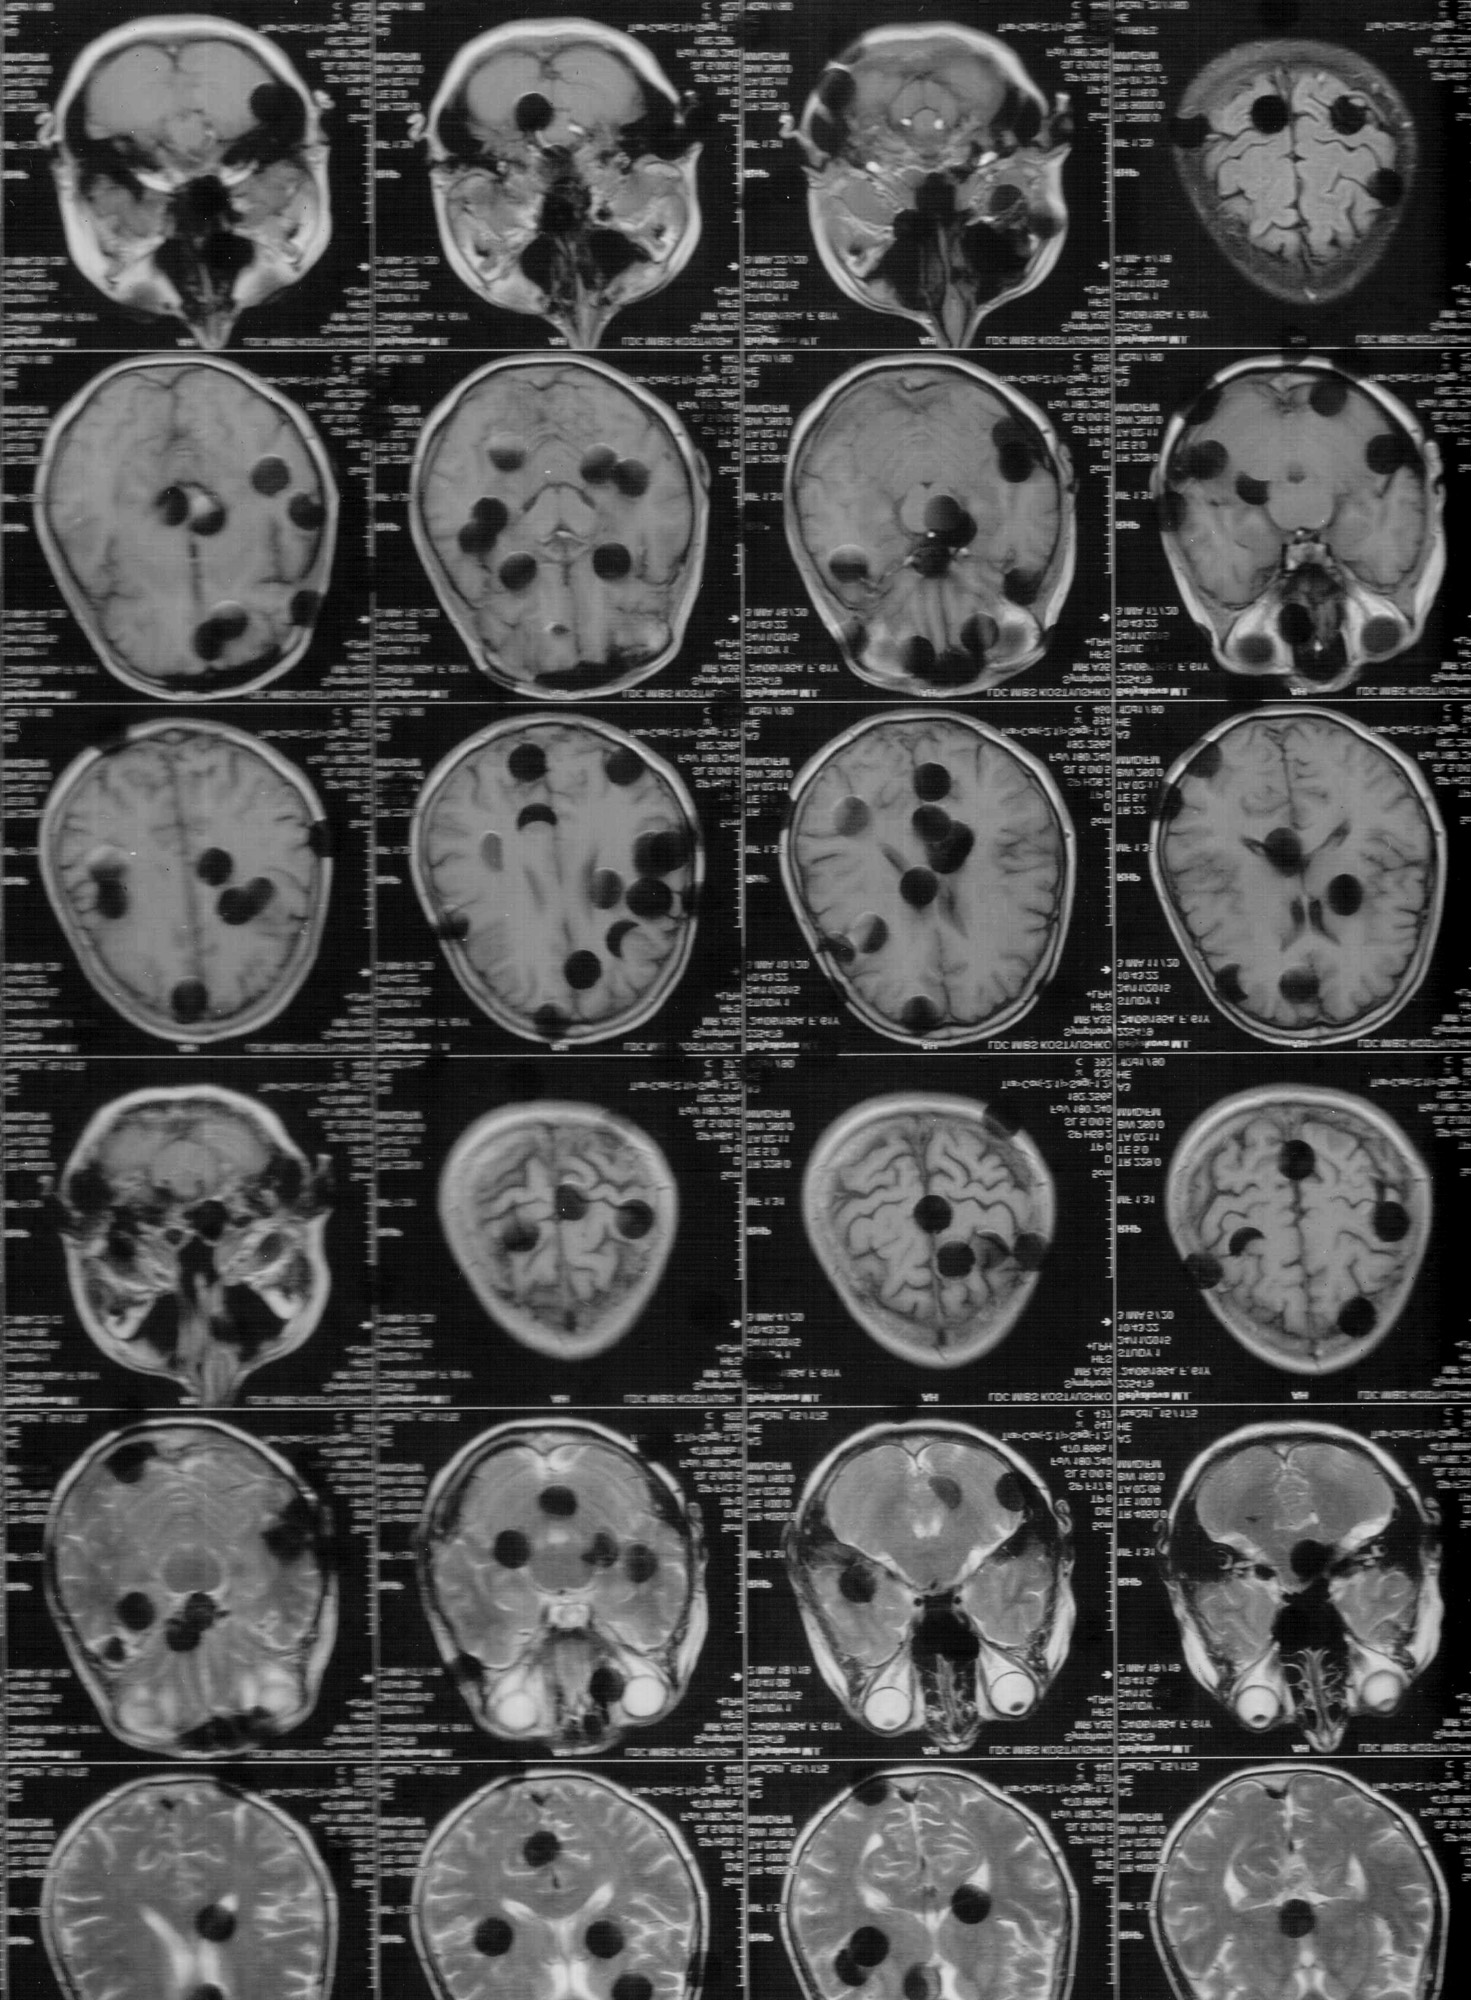

« This project reflects my inner perspective—an attempt to reveal what I conceal beneath the surface. It explores how uncertainty and fear shape my reality, examining both my physical and emotional state, where each day unfolds in anticipation.Soon, I will reach the age my mother was when she was diagnosed with Parkinson’s disease. We do not know whether I—or my children—have inherited it. All we can do is wait.Parkinson’s is a hereditary neurodegenerative condition that gradually impairs nerve cell function in the brain, affecting movement. Symptoms include tremor, rigidity, slowness, and balance disorders. Its exact causes remain unknown.In this work, metaphor becomes a way to navigate confusion and fear. Through photography, internal experiences take form and become visible. Working with family photographs, I deconstruct and alter their layers. Faces blur, gestures dissolve, and a distorted, trembling reality emerges. Photography moves beyond documentation to become a fragile surface of memory.I wonder whether I will recognize the boundary between “before” and “after.”Society often remains unprepared to confront Parkinson’s, perceiving it as something to conceal, even as a source of shame. The illness becomes a metaphor for instability and anxiety. This project seeks to challenge that perception, opening space for dialogue about vulnerability, adaptation, and inclusion. »